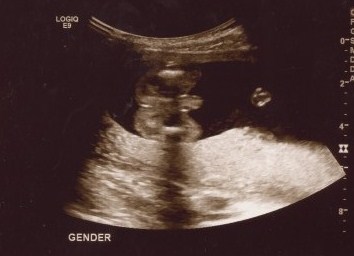

For an hour and a half today we watched, smiled, and cried at the images of our sweet baby boy. I learned a new kind of love today and my heart is full. I can't get enough of his little profile. We are so very blessed. Meet our little guy:

- In just a week and a half we will get to see you and find out whether you are a little boy or girl!